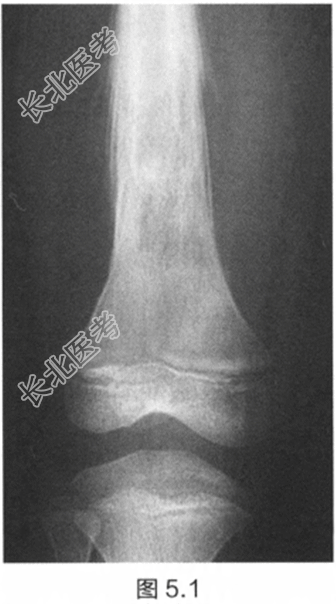

一名14岁男孩,全科医师发现他股骨中段有明显肿胀。患者还抱怨近几周内自觉疲劳和间歇性发热,导致无法进行少年足球训练。检查:触诊大腿中部,发现一压痛性肿块。推移肿块无活动性。腿部未发现神经或血管受累。初步检查显示白细胞(WBC)、红细胞沉降率(ESR)升高和贫血。股骨X线片如图5.1所示。

描述X线片所见。